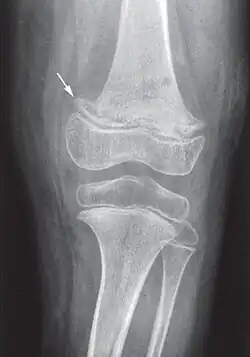

While many animals produce their vitamin C, humans and a few others do not.[2] Vitamin C, an antioxidant, is required to make the building blocks for collagen, carnitine, and catecholamines, and assists the intestines in the absorption of iron from foods.[2][4][5] Diagnosis is typically based on outward appearance, X-rays, and improvement after treatment.[2]

Diagnosis is typically based on physical signs, X-rays, and improvement after treatment.[2]